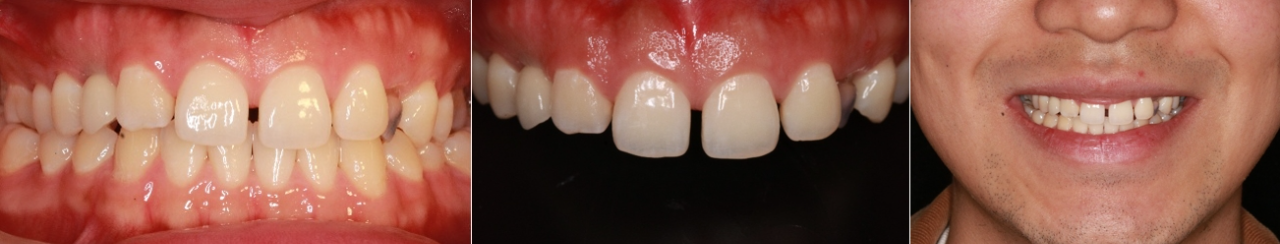

Patient: Male, 20 years old

Date: May 11, 2021

Diagnosis: Retained primary upper central incisors with esthetic and functional concerns

No major complications in opposing dentition